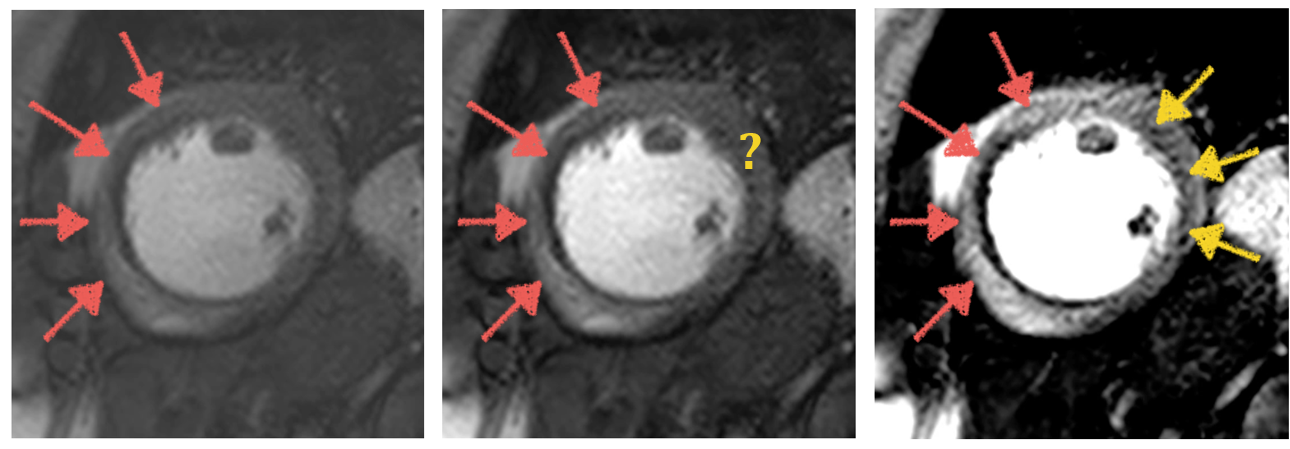

As discussed, due to its high diagnostic accuracy, stress perfusion CMR has become one of the methods of choice for the diagnosis of CAD. It has a class IA recommendation from the European Society of Cardiology (ESC) for the evaluation of patients with an intermediate pretest probability of CAD members2014. The main limitation of the modality is the difficulty of interpreting the images. The diagnostic accuracy has been shown to be highly dependent on the level of experience of the operator Villa2018. The difficulty of the interpretation of the images is visualised in Figure 3.2 which shows the same image with different levels of contrast windowing. The identification of perfusion defects, as indicated by the arrows, changes with different windowing. A potential solution to this is the quantitative analysis of the images which would add user-independence and reproducibility to the high clinical utility of the modality.

Refer to caption

Fig. 3.2: An example image demonstrating the difficulty of the visual assessment of perfusion CMR. The diagnosis of the patient from one-vessel disease (orange arrows) changes to two-vessel disease (orange and yellow arrows) with the narrowing of the contrast window. At an intermediate level of windowing (centre), the diagnosis is not clear.